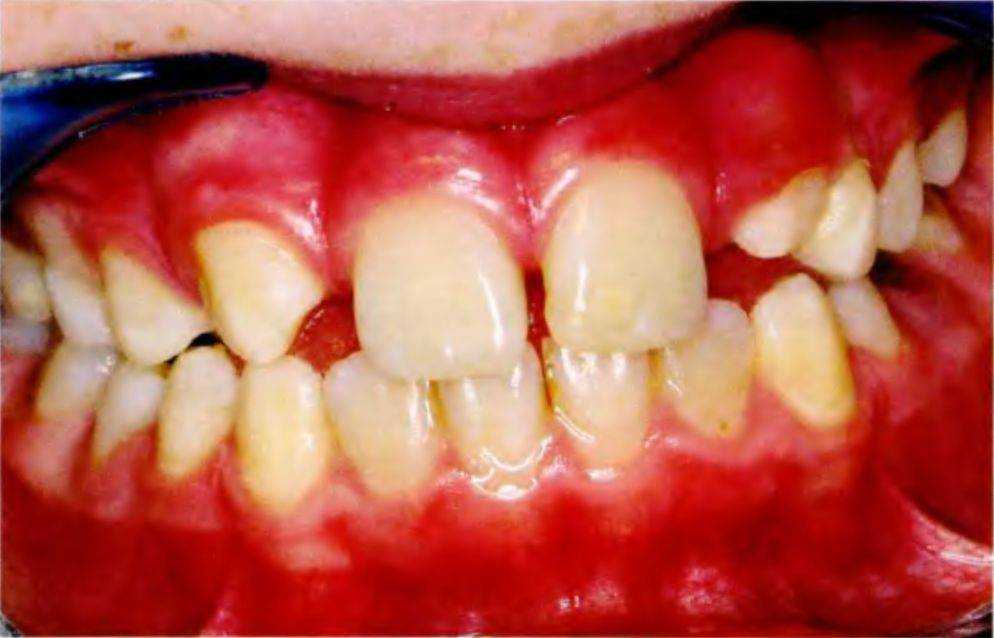

Рис. 5-За. Тринадцатилетний пациент с врожденным отсутствием боковых резцов верхней челюсти с помощью ортодонтических методов и последующее протезирование позволяют получить эстетически и функционально благоприятный долгосрочный результат. Таким образом достигается естественное положение клыков, оптимальное как с функциональной, так и с эстетической точки зрения. Только в нем они способны выполнять направляющую функцию при боковых и протрузионных движениях нижней челюсти. К передней группе зубов относится только медиальная часть клыка, дистальная часть относится к дистальной группе (рис. 5-2).

Ниже на примере клинического случая приведено поэтапное описание лечения пациента 13 лет с врожденным отсутствием верхних боковых резцов.

Рис. 5-3d. Клиническая картина после увеличения пространства ортодонтическими методами